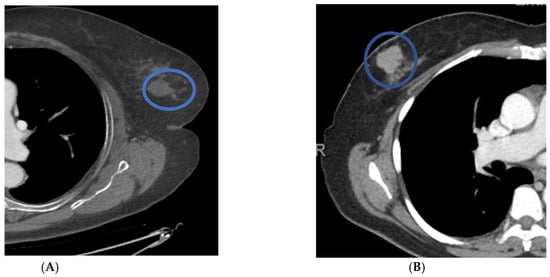

Figure 3. Distinguishing features of benign versus malignant masses on contrast-enhanced chest CT scans in axial projection. Patient (A) has a benign nodule with smooth borders and HUs of less than twenty. Patient (B) has a malignant nodule with lobular borders and HUs greater than twenty.

Forty-nine patients had masses on mammograms, of which 16% were cancer, and there were forty-four masses identified on CT, of which 20% were cancer. On chest CT, the average size of a cancerous mass was larger; no nodules less than 10 mm were cancer (p = 0.06) (Table 4) (Figure 2). The average HU of cancerous nodules was higher; no cancer had a HU of less than twenty-four (p = 0.003). Cancerous nodules were often lobular or spiculated (Figure 3). All nine cancerous nodules on CT were recommended for biopsy and two of thirty-five benign nodules were recommended for biopsy.

Masses were the most common finding on chest CT scans, prompting a recommendation for biopsy (12/20 (60%)). The cancerous masses were, on average, larger than non-cancerous masses and with higher Hounsfield units, as would be expected, as nodules with HUs less than 20 are often cysts. The majority of the cancerous masses were spiculated or lobular. The CT evaluation of HU and border contributed to the correct diagnosis for 33/35 benign masses and 9/9 cancerous. These results are promising but further research will determine if HUs could replace ultrasound exams for breast cancer evaluation.